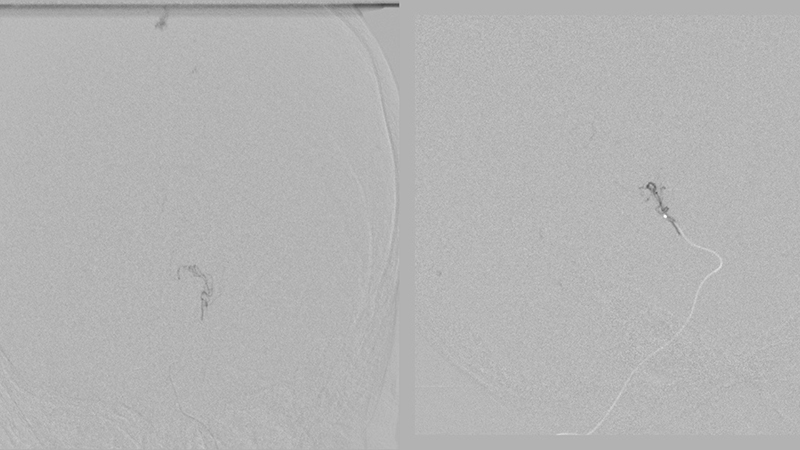

- Καθετηριασμός και εμβολισμός με κυανοακρυλική κόλλα θαλαμοδιατιτραινόντων κλάδων.

- Καθετηριασμός και εμβολισμός με κυανοακρυλική κόλλα υποεπενδυματικών κλάδων.

- Καθετηριασμός και εμβολισμός με κυανοακρυλική κόλλα οπισθιοπλαγίων χοριοειδών κλάδων.